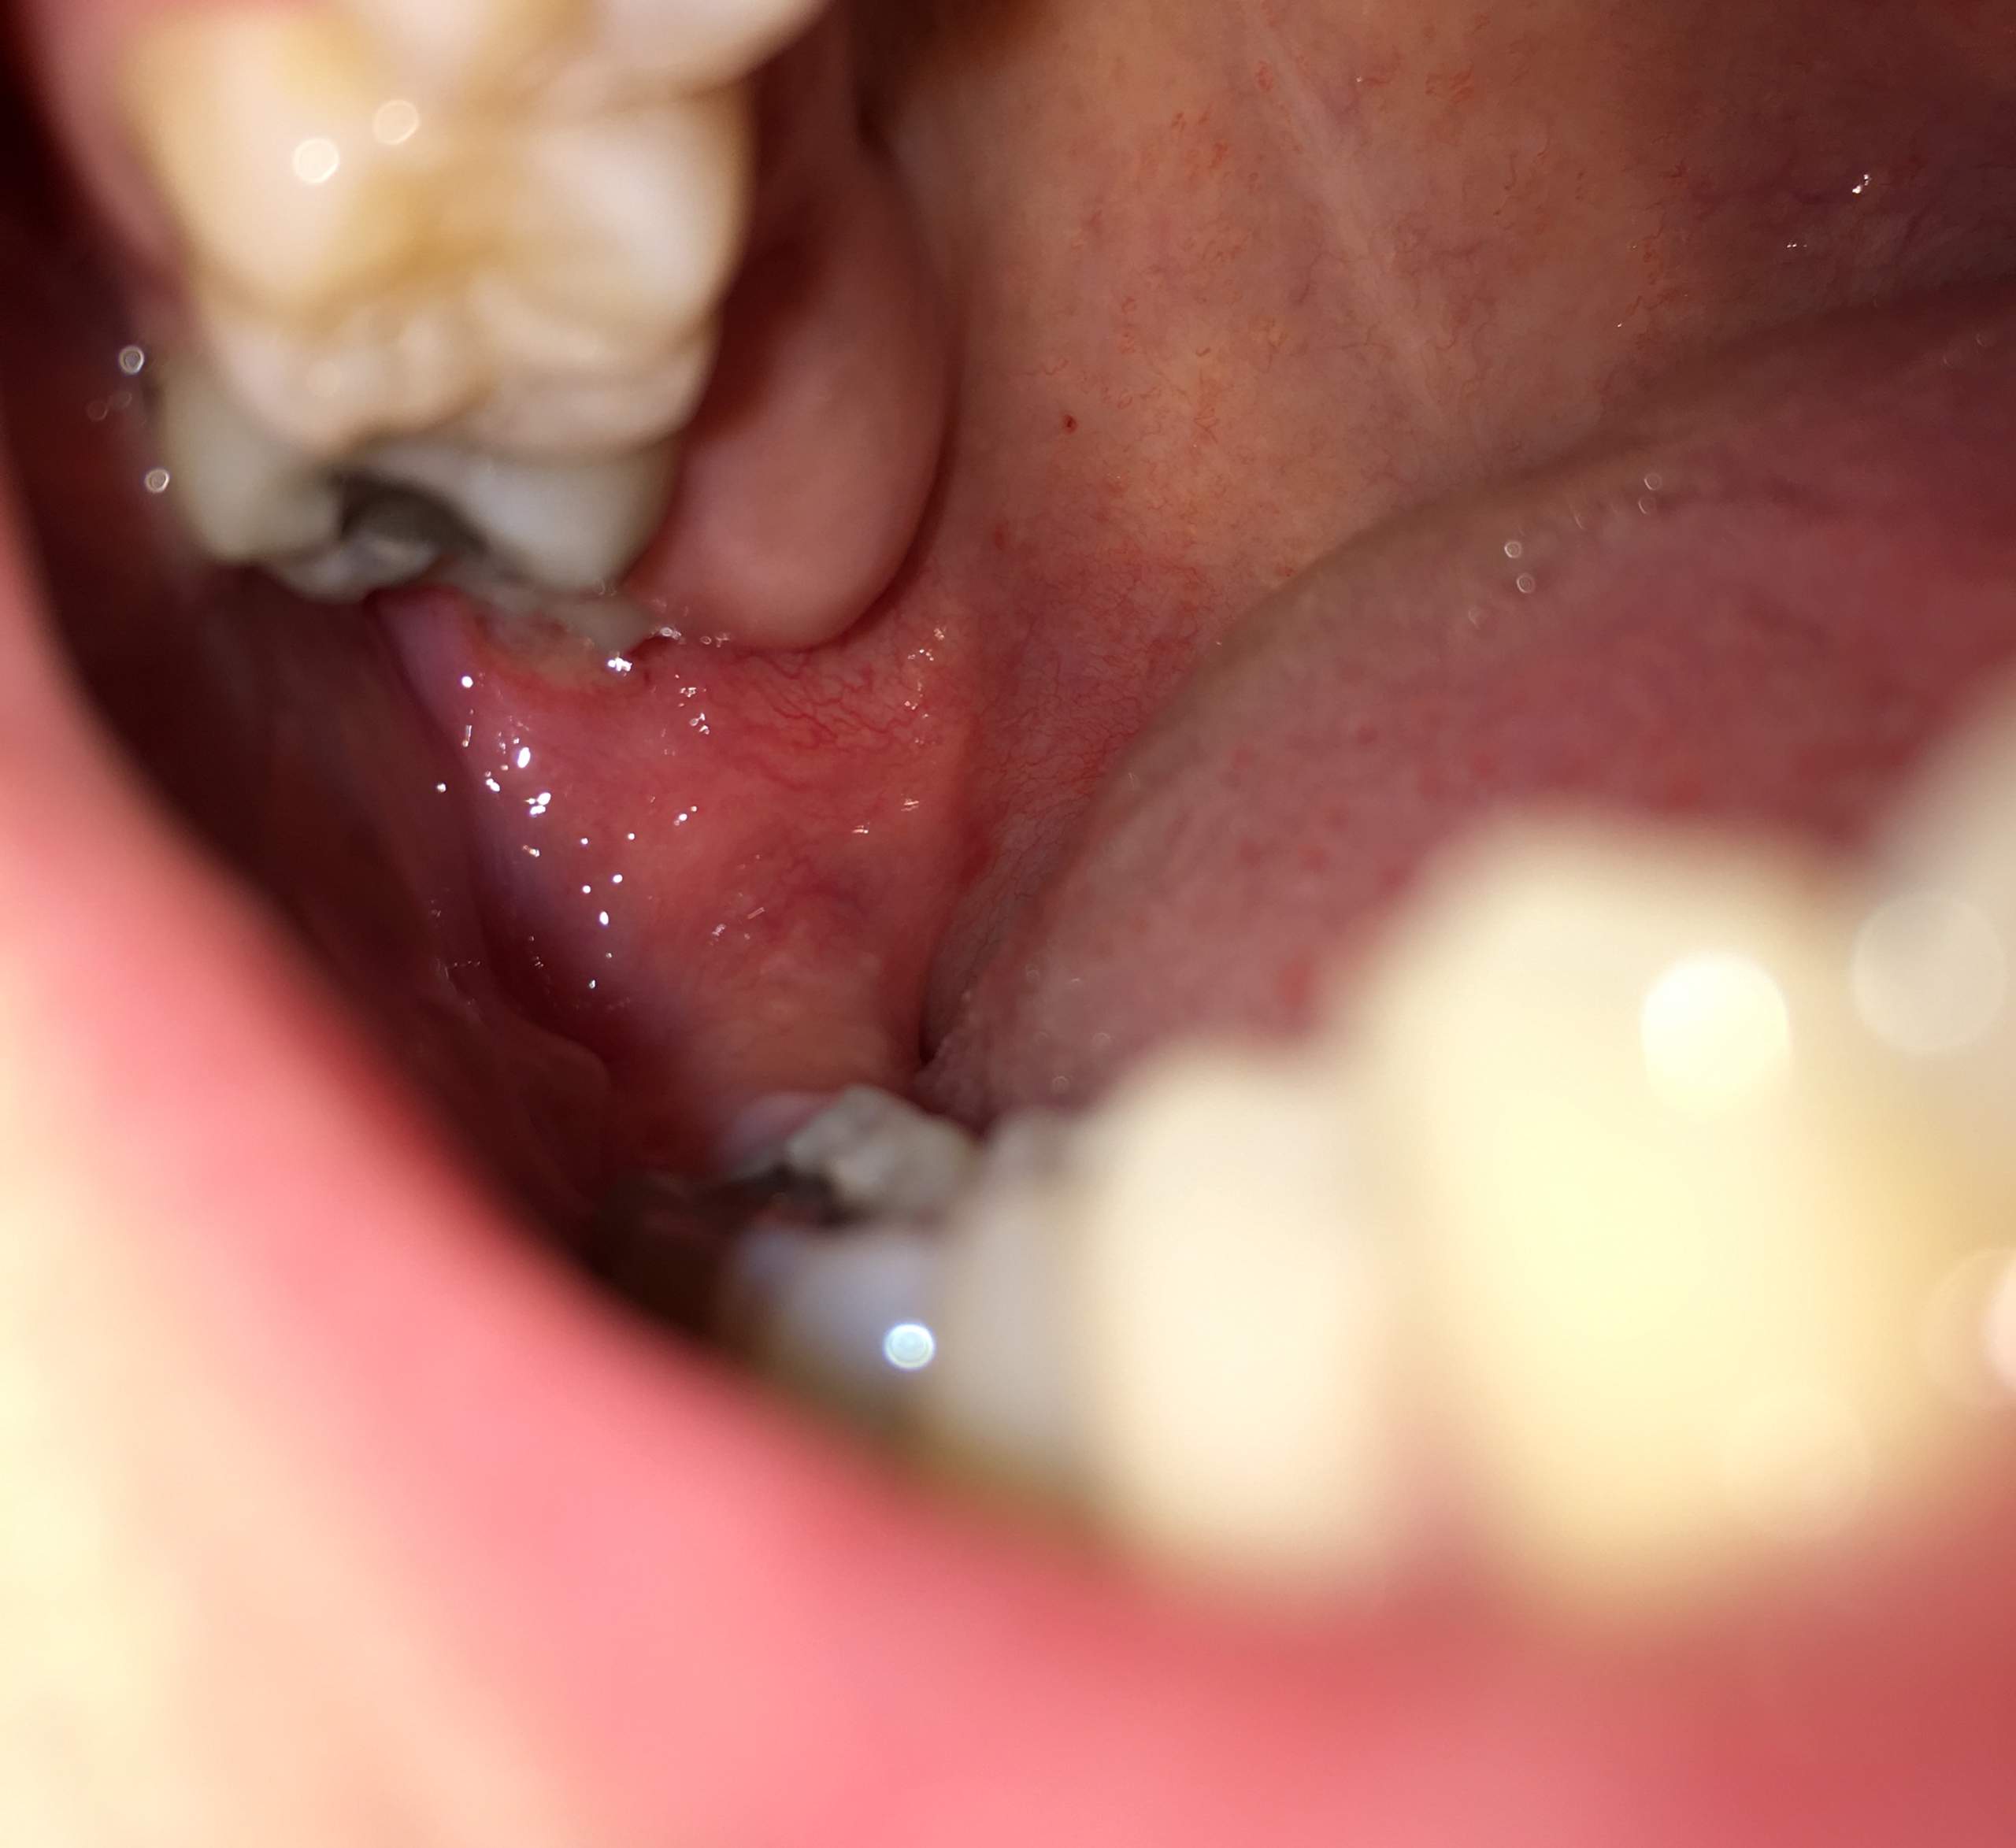

Tag 5 nach der Weisheitszahn-OP: Der Blut-Blues

Und hier kommt der Knackpunkt. Sagen wir mal, es ist Tag 5. Du denkst, du bist über den Berg. Du hast deine Schmerzmittel brav geschluckt, deine Mundspülung fleißig benutzt und sogar versucht, ein bisschen zu lächeln (was ehrlich gesagt mehr wie ein Grimasse aussieht).

Und dann… Blut. Plötzlich, ohne Vorwarnung, ist da wieder dieses kleine, fiese Rinnsal. Was zur Hölle, denkst du. Sollte das nicht längst vorbei sein?

Die üblichen Verdächtigen: Warum blutet es immer noch?

Okay, okay, ich will ja nicht komplett zynisch sein. Es gibt natürlich *logische* Erklärungen. Vielleicht hast du zu viel gemacht. Vielleicht hast du dich zu doll geschnäuzt (Ja, das ist ein Ding! Wer hätte das gedacht?). Vielleicht hast du einfach Pech. Die Blutgerinnung ist halt manchmal eine Diva.

Und natürlich gibt es die gefürchtete Alveolitis. Das böse A-Wort, das jeden Weisheitszahn-Patienten in Angst und Schrecken versetzt. Ich will es jetzt nicht zu sehr beschwören, aber wenn du *wirklich* starke Schmerzen hast, die nicht besser werden, und der Geruch aus deinem Mund einem Klärwerk gleicht, dann… ja, dann solltest du vielleicht doch mal deinen Zahnarzt anrufen.